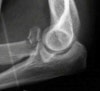

요골두의 분쇄 골절이 관찰됩니다.

X-ray : 전완부 골간막 손상(Essex-Lopresti injury)